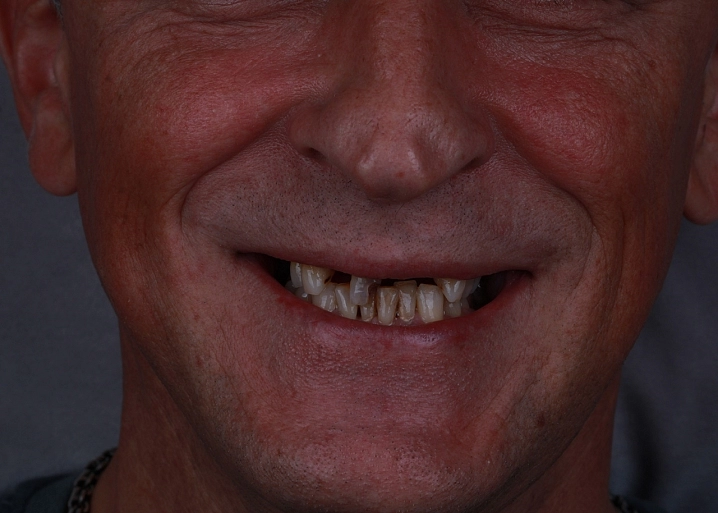

Специализация:

Восстановление зубов коронками и винирами, протезирование на имплантатах, изготовление съемных и несъемных протезов, решение проблем функциональности и эстетики зубочелюстной системы.